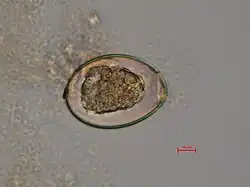

The adult worm is composed of three fairly distinct morphological segments: the scolex (head), the neck, and the lower body. Each side of the scolex has a slit-like groove, which is a bothrium for attachment to the intestine. The scolex attaches to the neck, or proliferative region. From the neck grow many proglottid segments which contain the reproductive organs of the worm. D. latum is the longest tapeworm in humans, averaging ten meters long. Unlike many other tapeworms, Diphyllobothrium eggs are typically unembryonated when passed in human feces.[4]